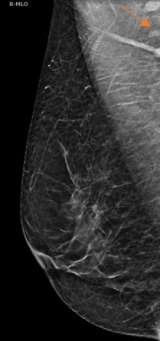

The axilla is partially imaging during mammography and axillary lymph nodes are commonly seen. Evaluation of lymph nodes on mammography involves assessment of laterality and lymph node morphology. Benign axillary lymph nodes (figure 1) are oval in shape, typically measuring less than 2 cm, with a preserved fatty hilum which appears as radiolucent notch on mammogram. Increased lymph node size or density can be abnormal, requiring additional evaluation1. In the case of abnormal lymphadenopathy, attention should be made to whether the lymph nodes are unilateral or bilateral as this can help narrow the differential diagnosis1,2.